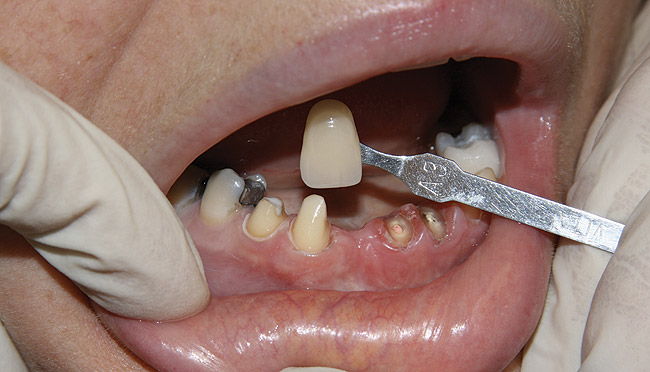

Figure 11  Original feldspathic porcelain crown placed by restorative dentist, tooth No. 9—facial view.

Figure 11

Figure 12  Localized moderate gingival inflammation on facial aspect of No. 9 (2 years post-cementation).

Figure 12

Emergency endodontic treatment had been completed to manage the traumatically exposed root canal; Figure 10 shows the pre-treatment (Ellis Class III crown fracture) and post–endodontic-treatment periapical views of tooth No. 9. The restorative dentist temporarily cemented a glass-reinforced fiber post and used a fiber-reinforced composite core buildup material as an immediate provisional. Several weeks later, a provisional bis-acryl temporary crown on No. 9 was cemented on a larger-diameter glass-reinforced fiber post retaining a new fiber-reinforced composite core. Figure 11 shows the final feldspathic porcelain crown placed by the restorative dentist. During the fabrication and cementation of this crown, the remaining root appeared intact and the tooth was asymptomatic.

Two years later, however, the patient returned to her restorative dentist’s office complaining that “something felt different” on tooth No. 9. Localized moderate gingival inflammation was present on the facial aspect of No. 9 (Figure 12). A straight facial probing depth of 6 mm and severe bleeding on probing were also evident facially, suggesting a vertical root fracture.